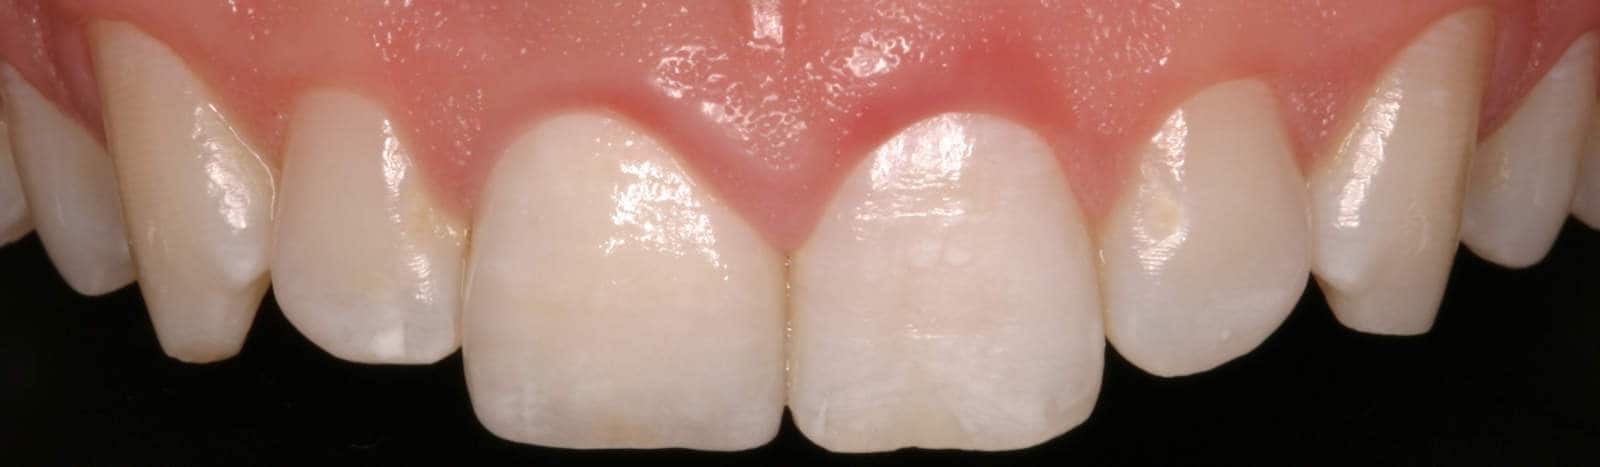

After: Followed by delivery of a custom ceramic post/core foundation, and a bonded all-ceramic full coverage single restoration (crown).